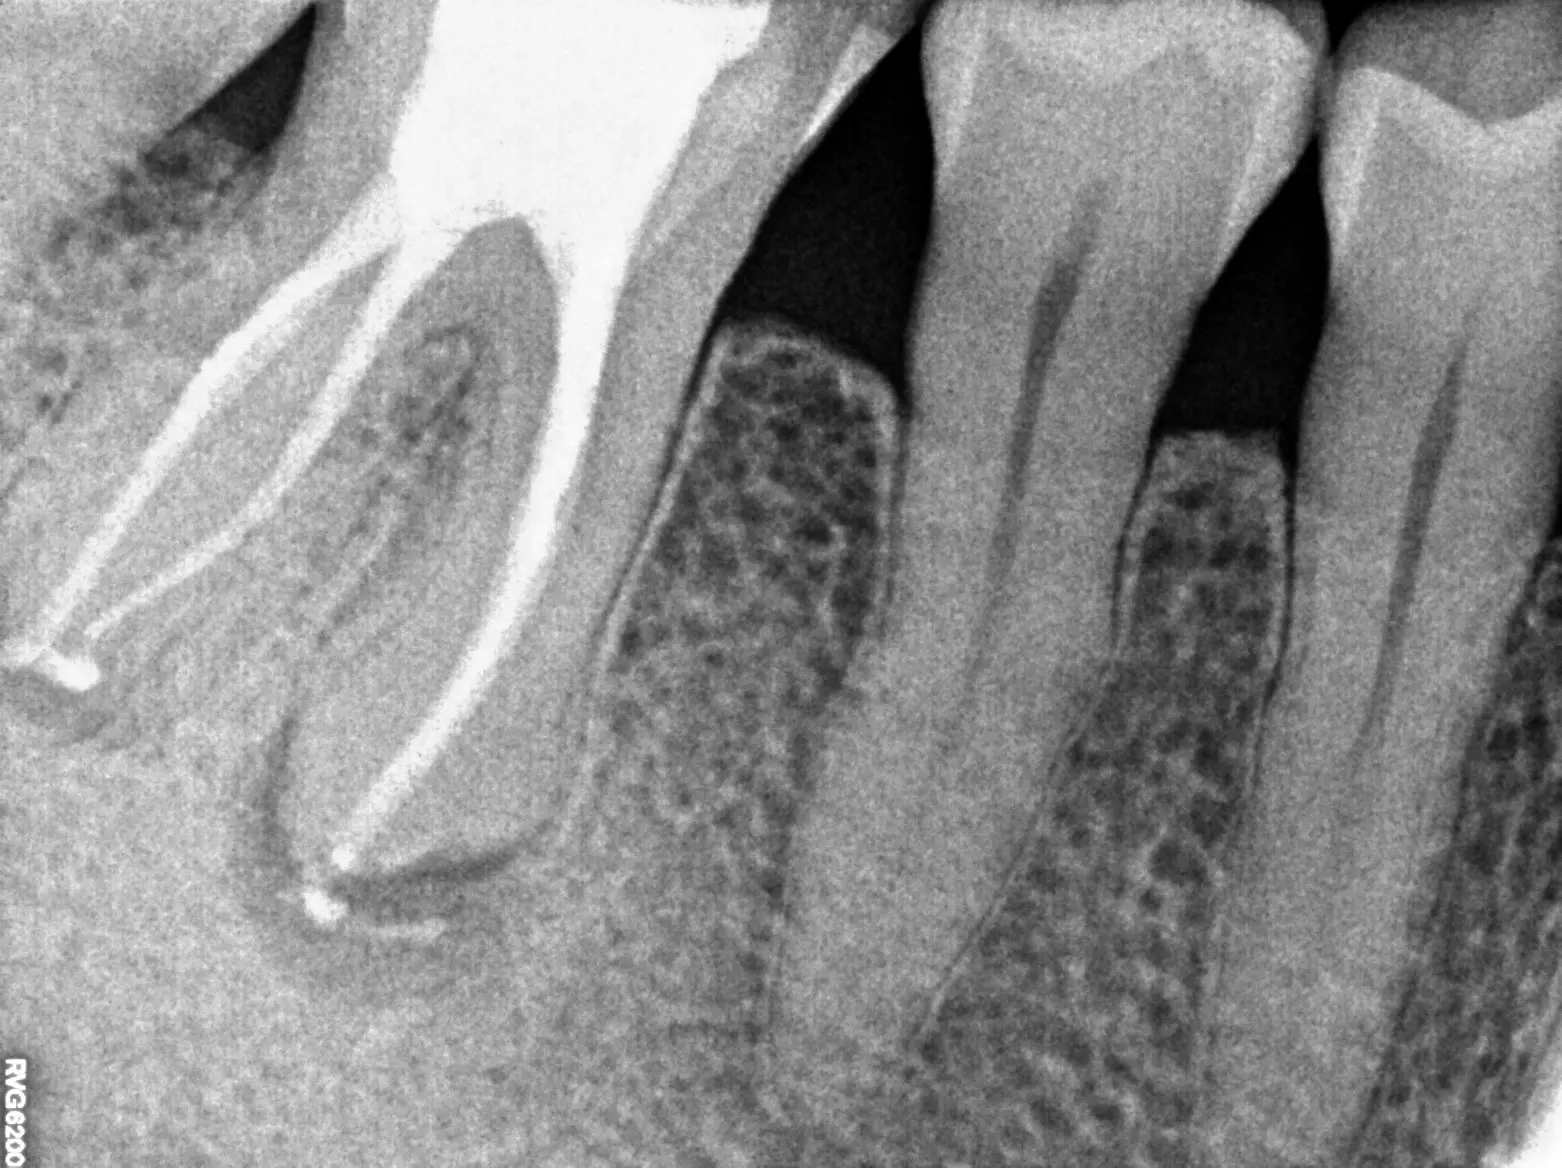

Retreatment involves the doctor reopening the tooth to gain access to the root canal filling material. The restorative material will be removed. The doctors will clean your canals and examine the problematic tooth. Once cleaned, the doctor will fill and seal the canals and place a temporary filling in the tooth.